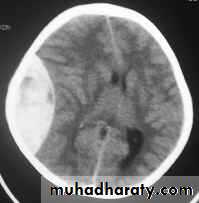

Chronic Subdural Haematoma

Most common in infants and in adults over 60 years of age secondary to SLIGHT blow to the head which may pass unnoticed.Source of bleeding (haematoma): usually from bridging veins as they pass to the venous sinuses.

The patients present with progressive neurological deficits more than 3 weeks after the trauma.

The initial head injury is often completely forgotten.

CT scan: the acute clotted blood is initially appears white (hyperdence), but as it liquefies, it slowly becomes black (hypodense).

They should be drained if they continue to enlarge.

They are evacuated by drilling burrholes over the collection and washing it out with warmed saline.